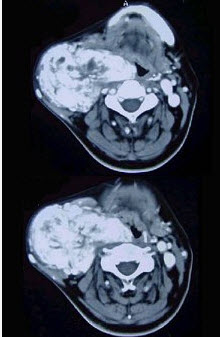

45岁,男性,颈部渐进性增大包块,CT增强扫描如图所示,请选择最可能诊断()。

A、颈部肿大淋巴结

B、颈动脉夹层瘤

C、神经鞘瘤

D、颈动脉体瘤

E、甲状腺癌

D